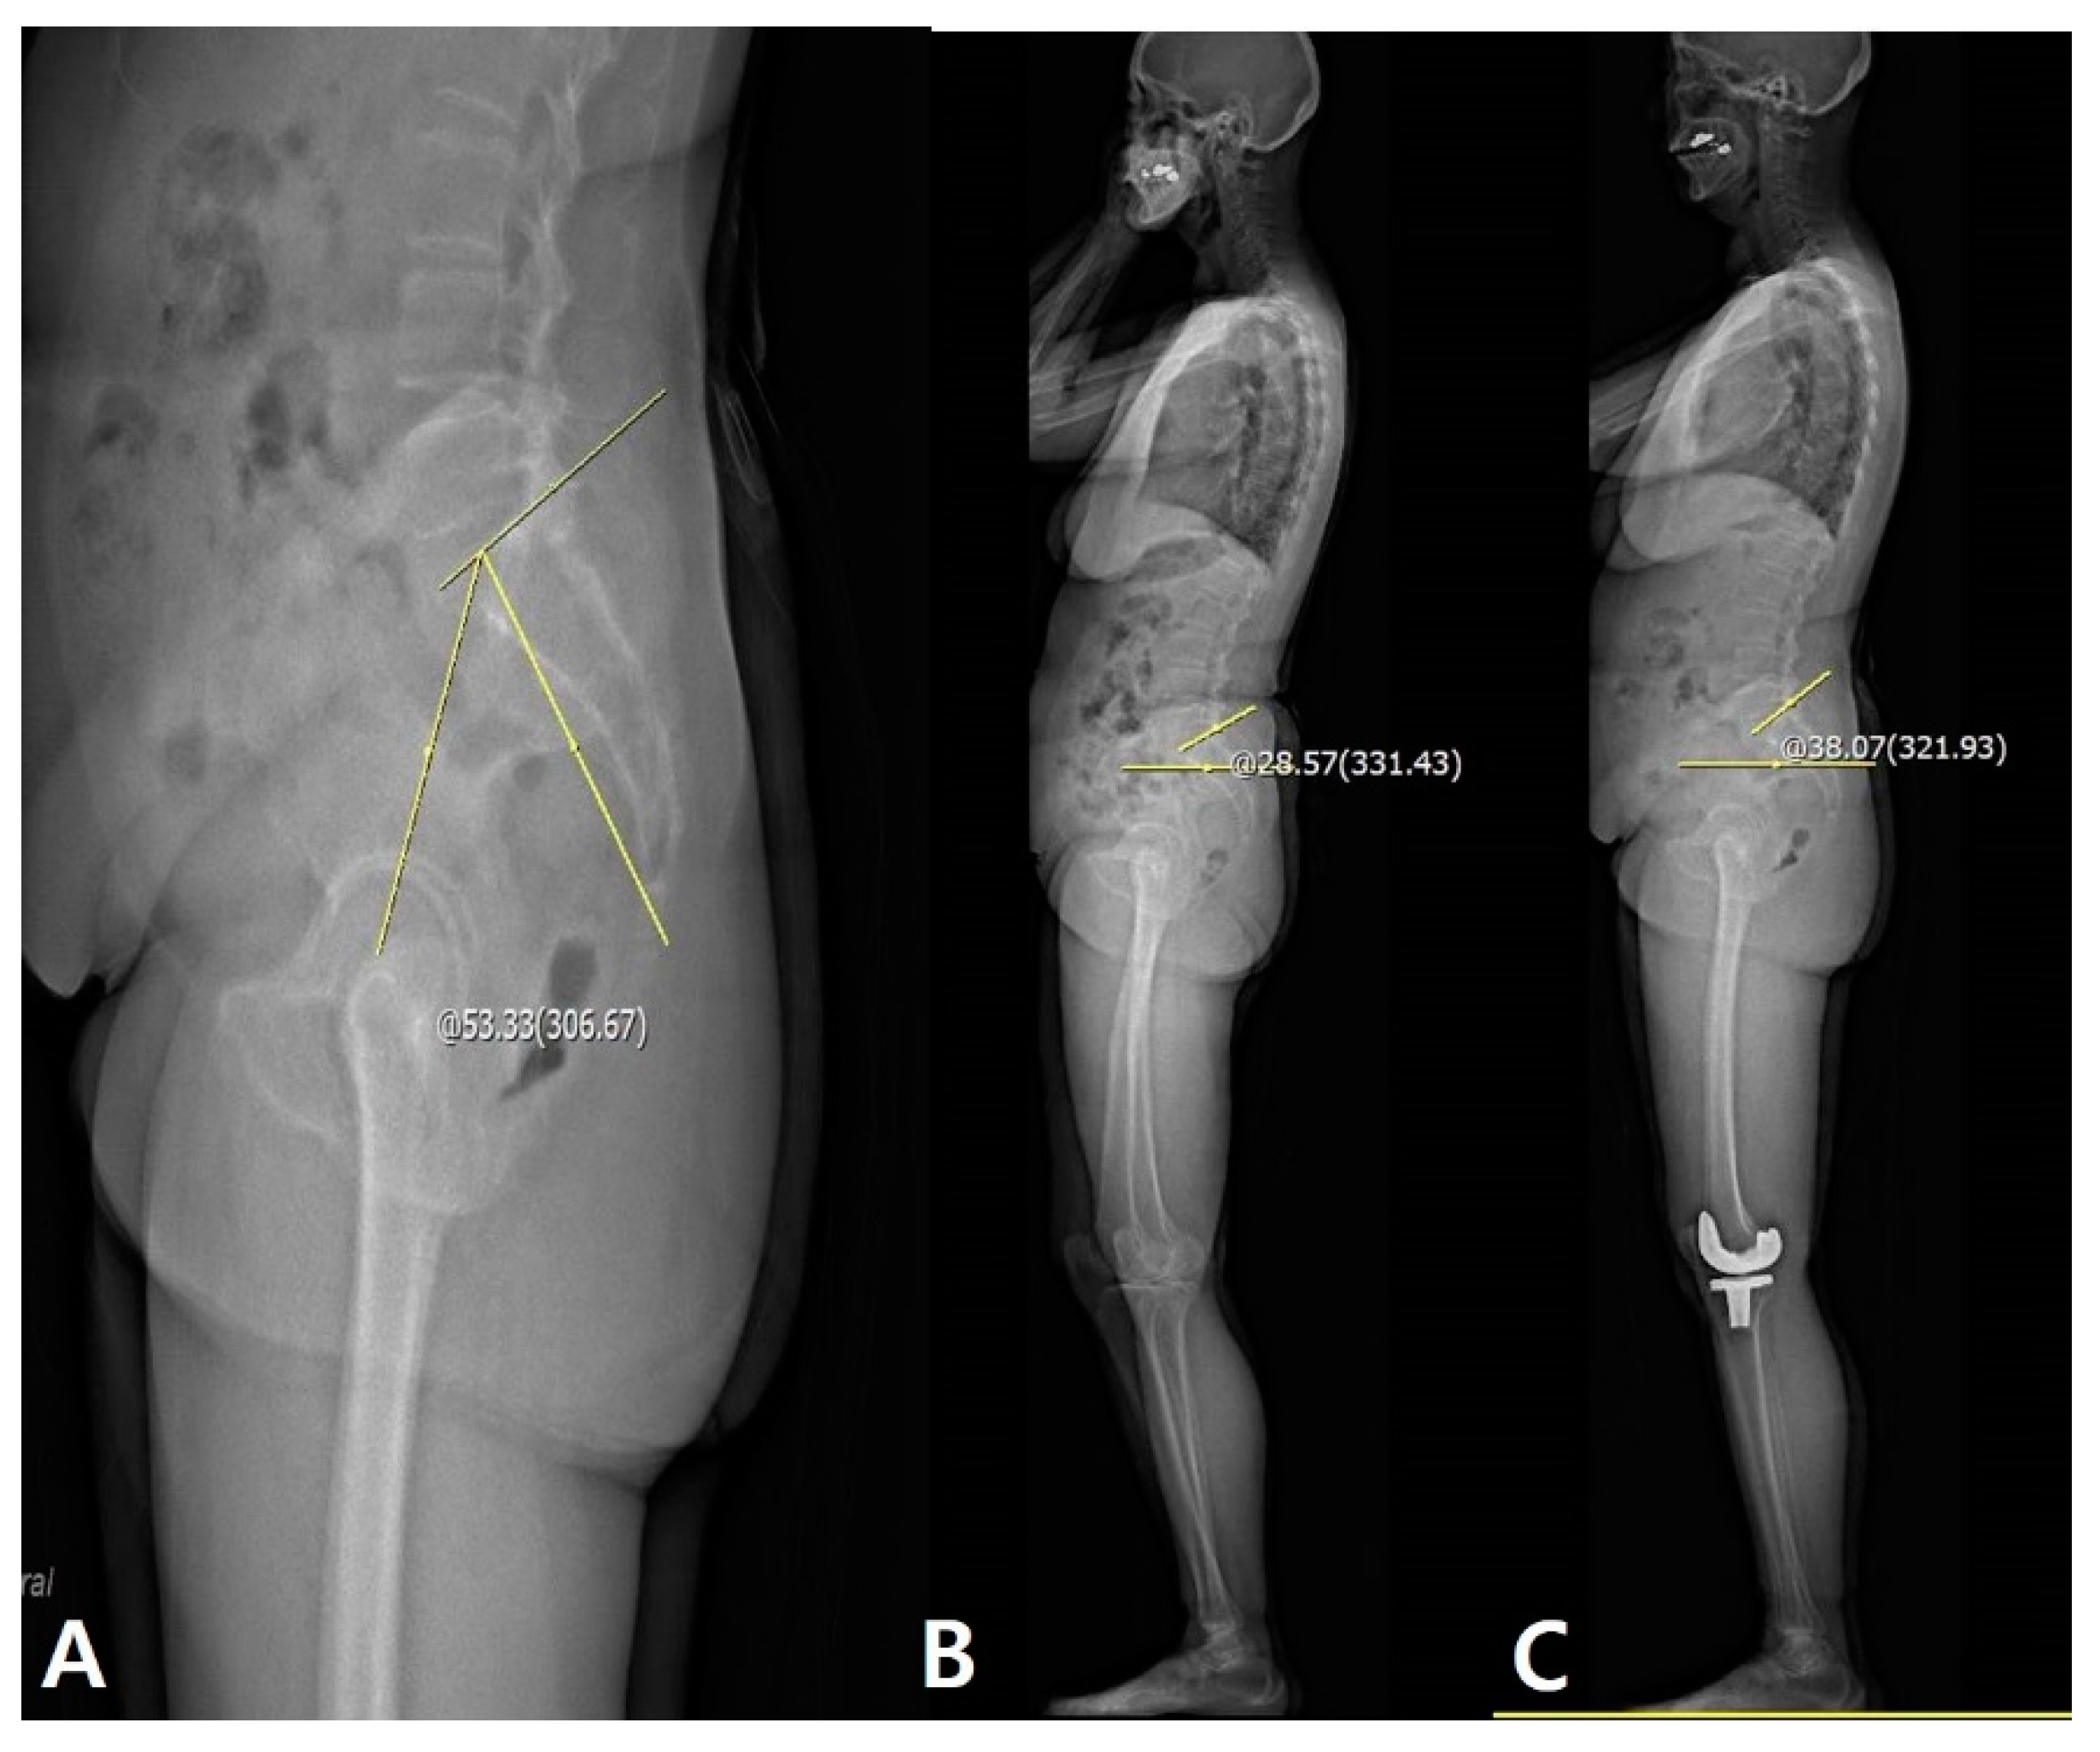

Figure 4. Patient with larger pelvic flexibility (PF) improved sagittal pelvic alignment, such as increased SS, after TKA. (A) Measurement of PF: 53.33°. (B) Measurement of preoperative SS: 28.57°. (C) Measurement of postoperative SS: 38.07°. The yellow line and circle are the measurement about pelvic incidence and sacral slope.

The correlations between the PF and other sagittal parameters are summarized in Table 3. Although there were correlations between PF and ΔSS between preoperative and 1-year postoperative data (p < 0.001, PCC: −0.362), other sagittal parameters were not correlated with the PF. Linear regression analysis for the identification of cause–result relationships revealed that larger PF significantly increased SS after TKA (p < 0.001, β = −0.208) (Table 3 and Table 4, Figure 4).